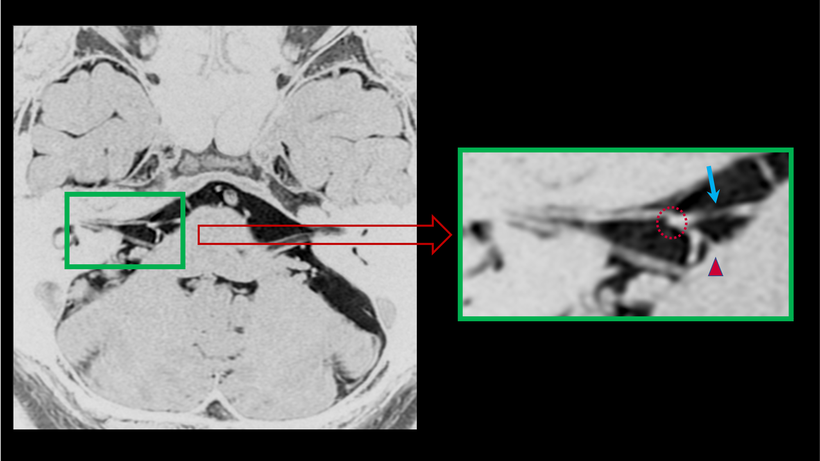

【 顔面痙攣の起きている事がわかるMRI画像-1 】

一般的に多く認められる画像所見です。聴神経(▲)の上を走行している顔面神経(▲)が認められます。蛇行した血管(動脈/↑)が、顔面神経の根元(▲)に当たっており圧迫している所見が認められます(点線○)。